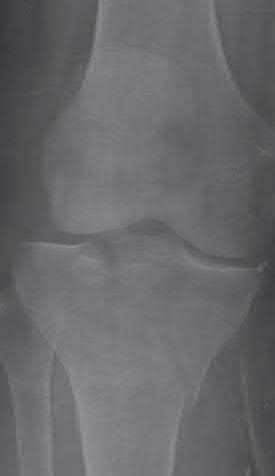

Question 16

During a posterior-stabilized total knee arthroplasty, the surgeon evaluates the gaps using trial components.

The assessment demonstrates that the extension gap is perfectly balanced and rectangular, but the flexion gap is excessively tight. What is the most appropriate isolated next step to balance the knee?

Explanation

If the flexion gap is tight but the extension gap is balanced, the surgeon must alter the flexion gap without affecting the extension space. Downsizing the femoral component (using the same posterior referencing guide, or using an anterior referencing system) translates the posterior condylar surface anteriorly, effectively increasing the flexion space while leaving the distal femoral resection (extension gap) unchanged.